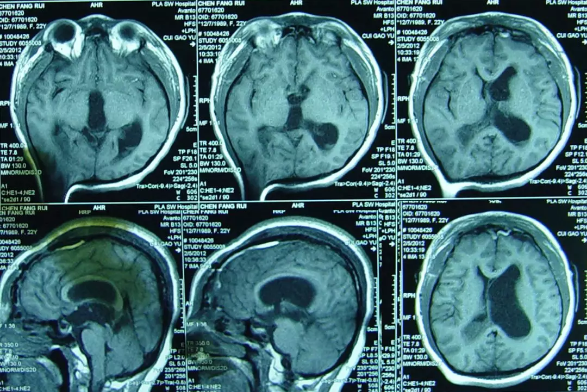

但内镜造瘘术后2小时出现了癫痫发作,意识模糊,查头颅CT:内镜造瘘术后状态,双额部硬膜下血肿(图-1)。

图-1:2012年4月28日头CT